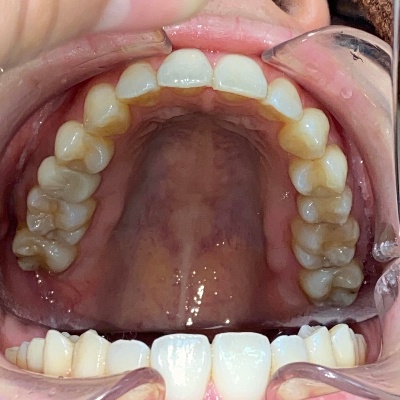

上下前歯の歯並びがガタガタしているのが気になる、きれいにしたいとのご希望で来院されました。

来院時の歯並び写真